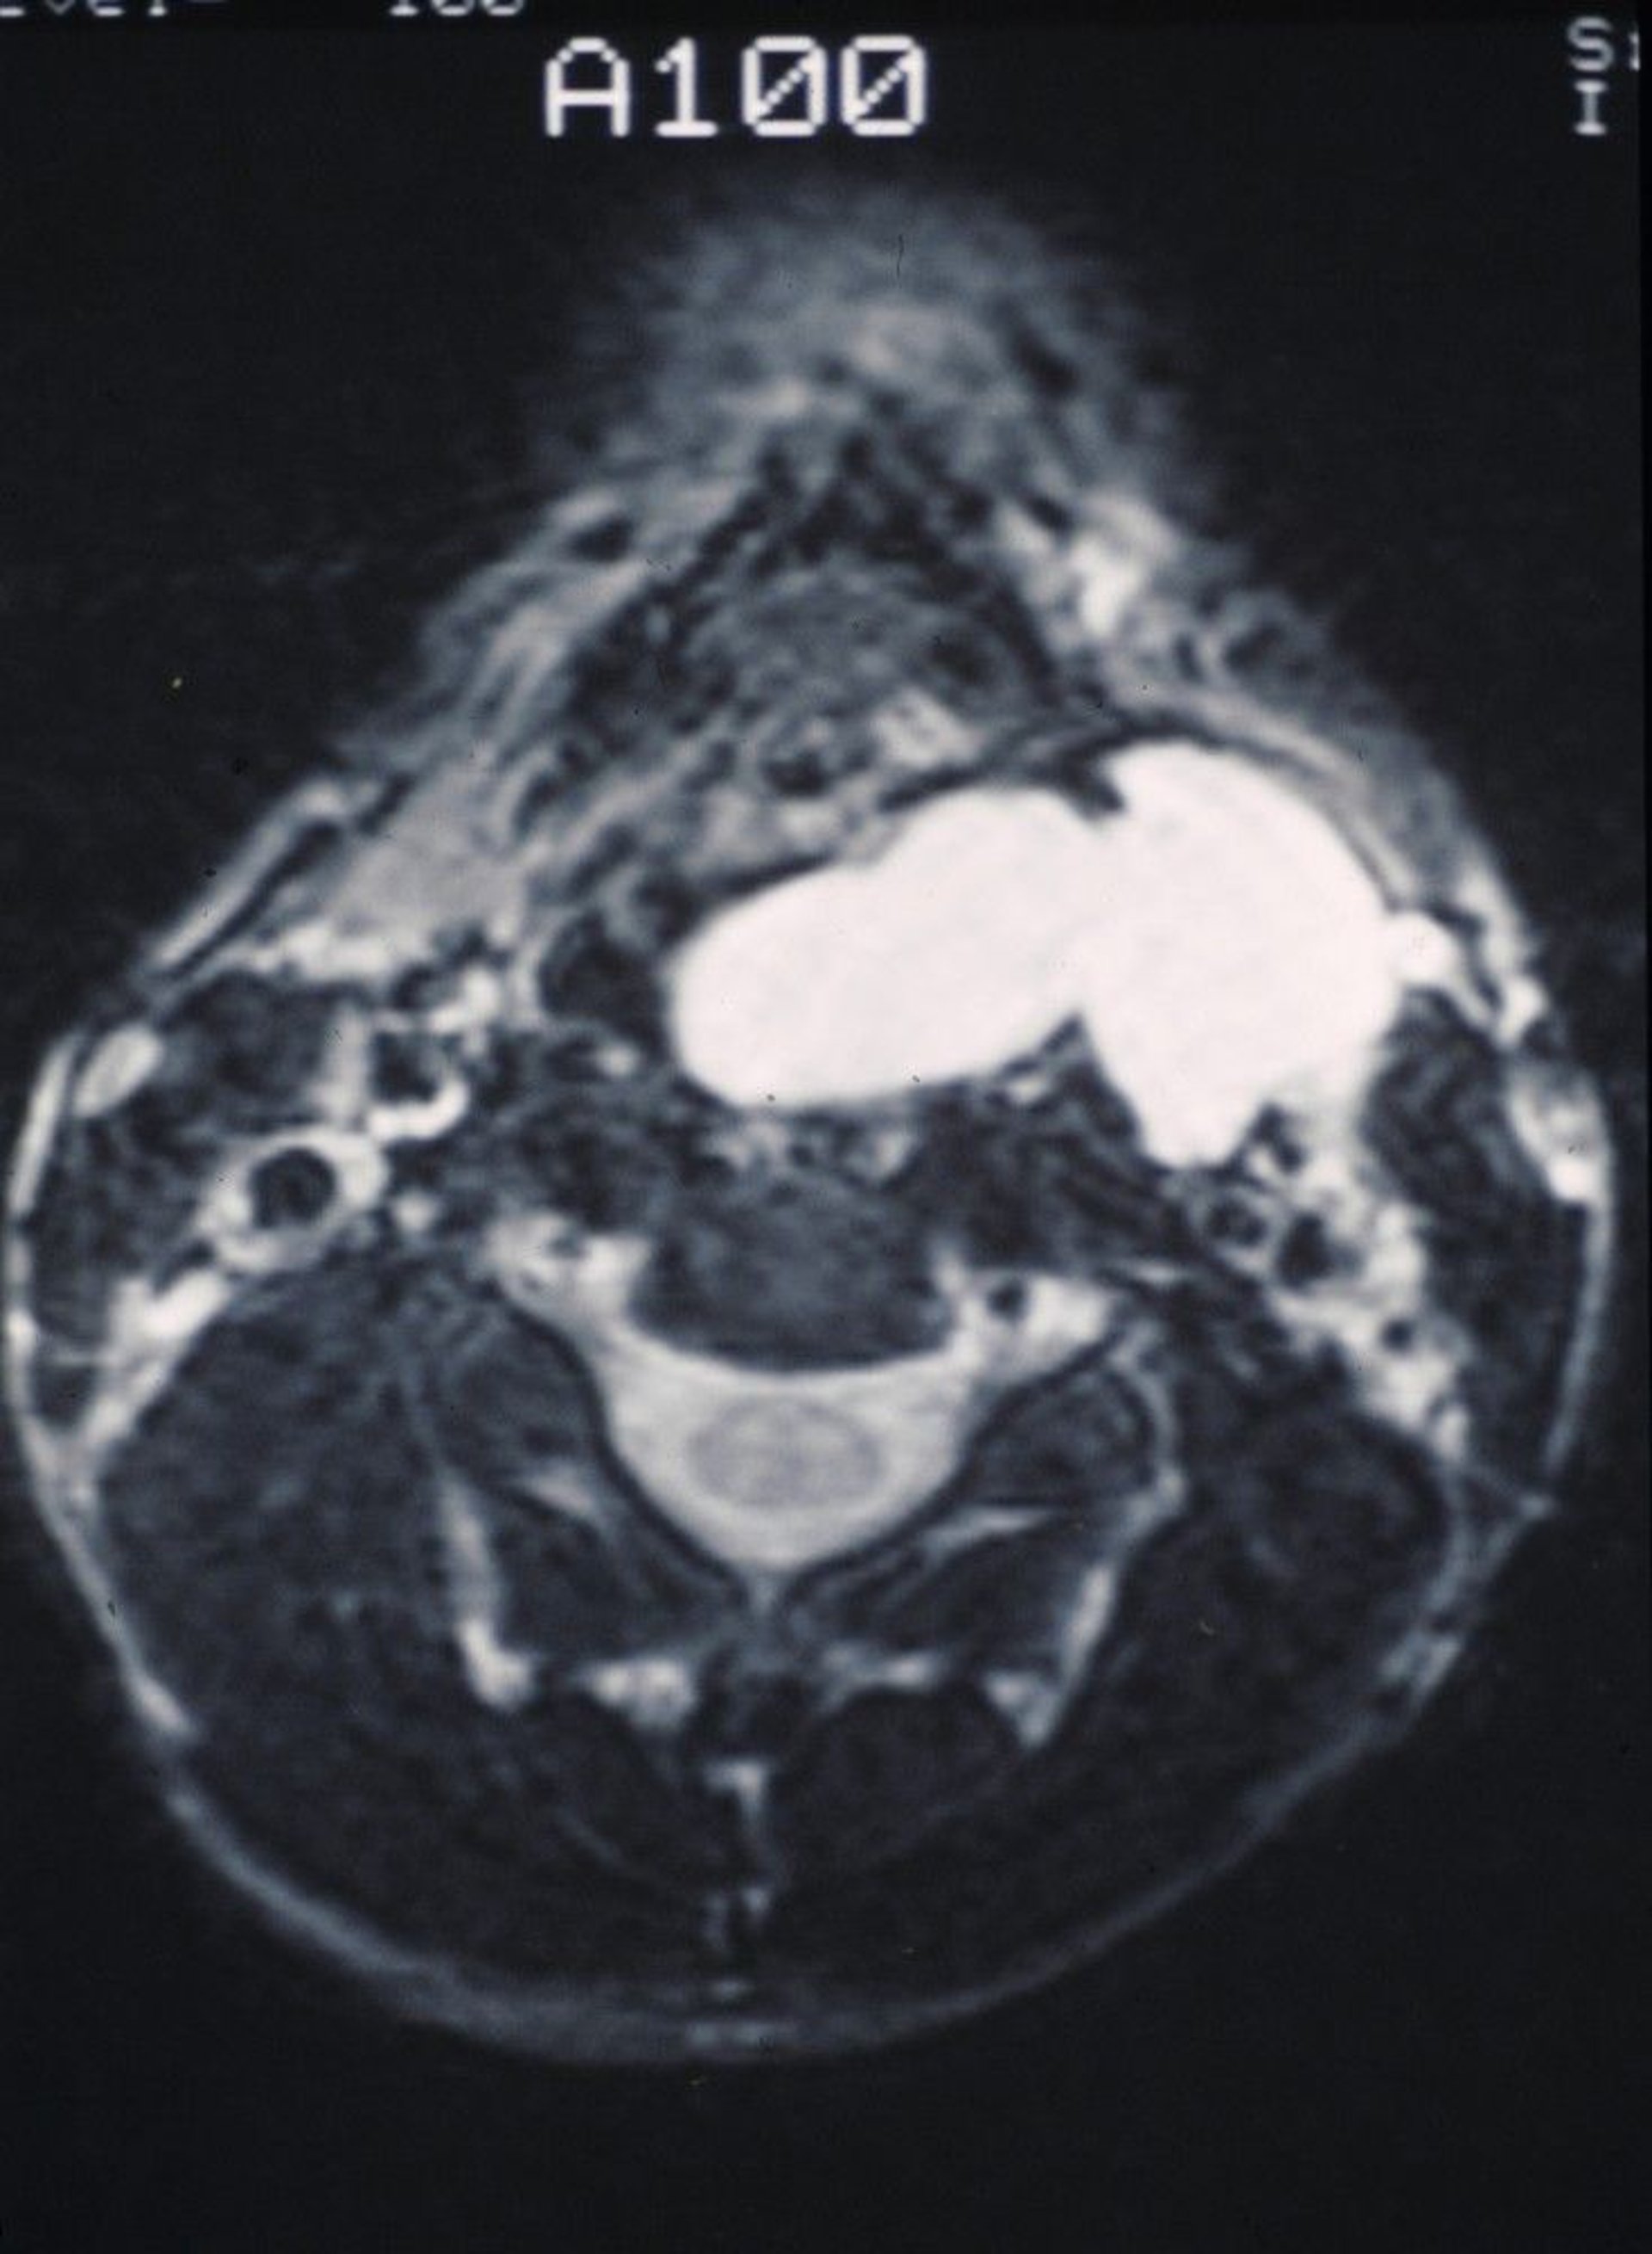

This MRI scan shows a smooth mucus-filled laryngocele bulging into the throat and outward into the neck.

Image provided by Clarence T. Sasaki, MD.